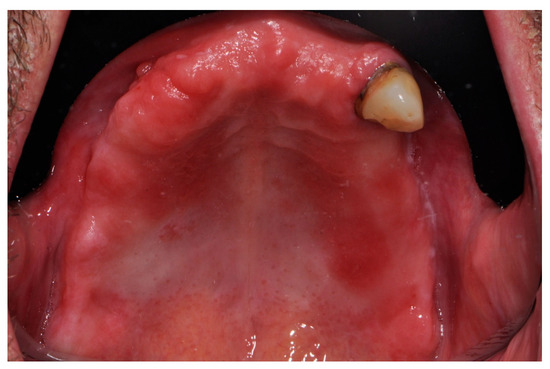

2.2. Surgical Procedures and Post-Operative Care